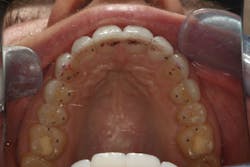

We digitally analyze our esthetics and smile design using the Dawson Diagnostic Wizard (the Dawson Academy). One of our biggest esthetic concerns in this case was caused by a functional issue. As you can see in the photos (figures 1 and 2), the patient has significantly more attritional wear on the right side versus the left. Due to the wear, the right anterior teeth have suffered from more compensatory eruption than the left, which results in uneven gingival architecture and esthetically displeasing length-to-width ratios of the anterior teeth (figures 3 and 4).

When we start to look at our occlusal shots (figures 5 and 6), it is obvious that we have some acidic erosion into dentin as well as significant wear facets from attrition. The pulp chambers of teeth Nos. 8 and 9 are now visible due to the loss of lingual tooth structure.